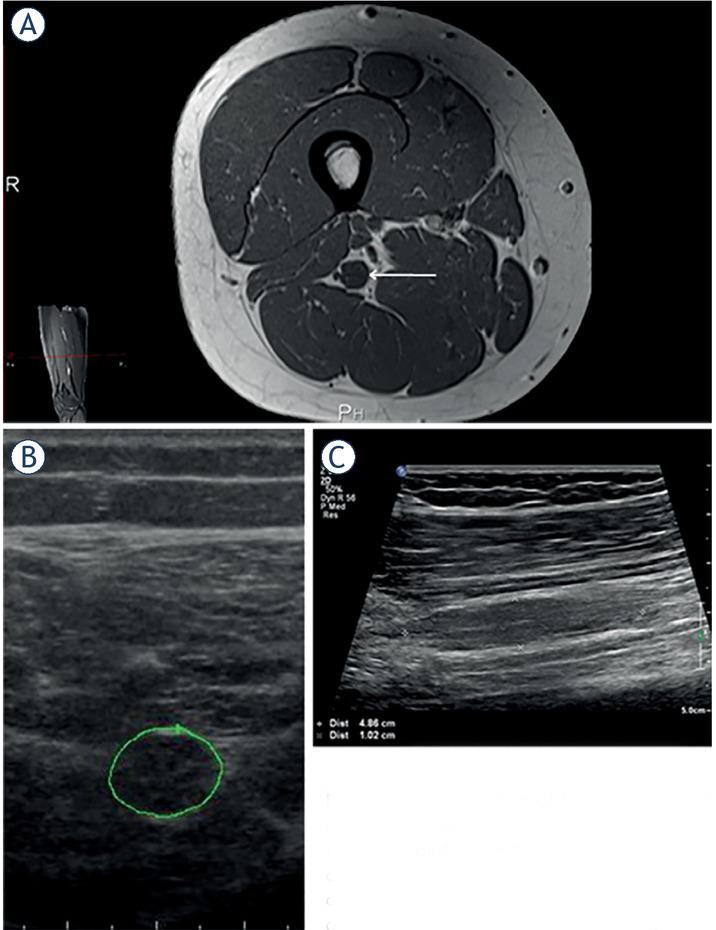

The second group consisted of three girls (patients #6, 7, 10) presenting in the first decade of life with unilateral foot drop. Each of them had several lumbo-sacral spine MRs that all proved negative, and their PNTs were not diagnosed until they presented to our US laboratory 8–15 years after symptom onset. At that time their clinical features were unchanged for several years, so none of them decided to have a nerve biopsy to establish a histological PNT diagnosis. Nevertheless, we believe these 3 patients most probably have sciatic nerve perineurioma.11 One of them (patient #10) had two PNTs, separated by 20–30 cm segment of US relatively normal sciatic nerve. Using US we demonstrated the more distal PNT of the tibial portion of sciatic nerve (Figure 2). Additional more proximal PNT affecting fibular portion of sciatic nerve, and causing foot drop was found on MR.

Comparison of transverse image of the sciatic peripheral nerve tumour (PNT) on (A) magnetic resonance (MR) T1 (arrow) and (B) ultrasonography (US). (C) Longitudinal US view of PNT in the middle thigh (A – small picture on the left), affecting the tibial portion of sciatic nerve. In this 22-year-old girl MR revealed at the exit of sciatic nerve from the pelvis another PNT affecting its fibular portion, and causing right foot drop of 14 years duration (patient #10, Tables 2–3). Based on clinical and imaging features in this patient diagnosis of probable perineurioma was made.